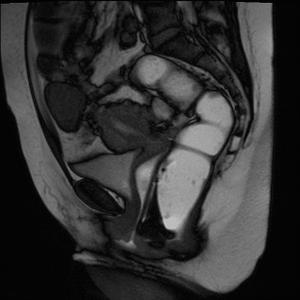

2.子宫脱垂。目前超声对子宫脱垂分度尚无统一定论。

3.直肠膨出:又称为阴道后壁膨出,亦称为直肠阴道膨出或者直肠阴道疝。该膨出物与肛管约呈90度夹角。